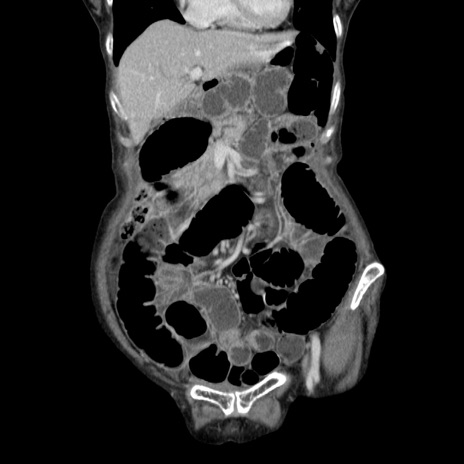

症例25(冠状断像)

【症例】80歳代女性

【主訴】胸のつかえ感

【現病歴】約9時間前に食後から胸のつかえた感じあり、嘔吐あり、来院。

【既往歴】胃癌(全摘)、胆摘、虫垂炎

【身体所見】心窩部に圧痛あり、反跳痛なし。

【データ】WBC 5700、CRP 0.05